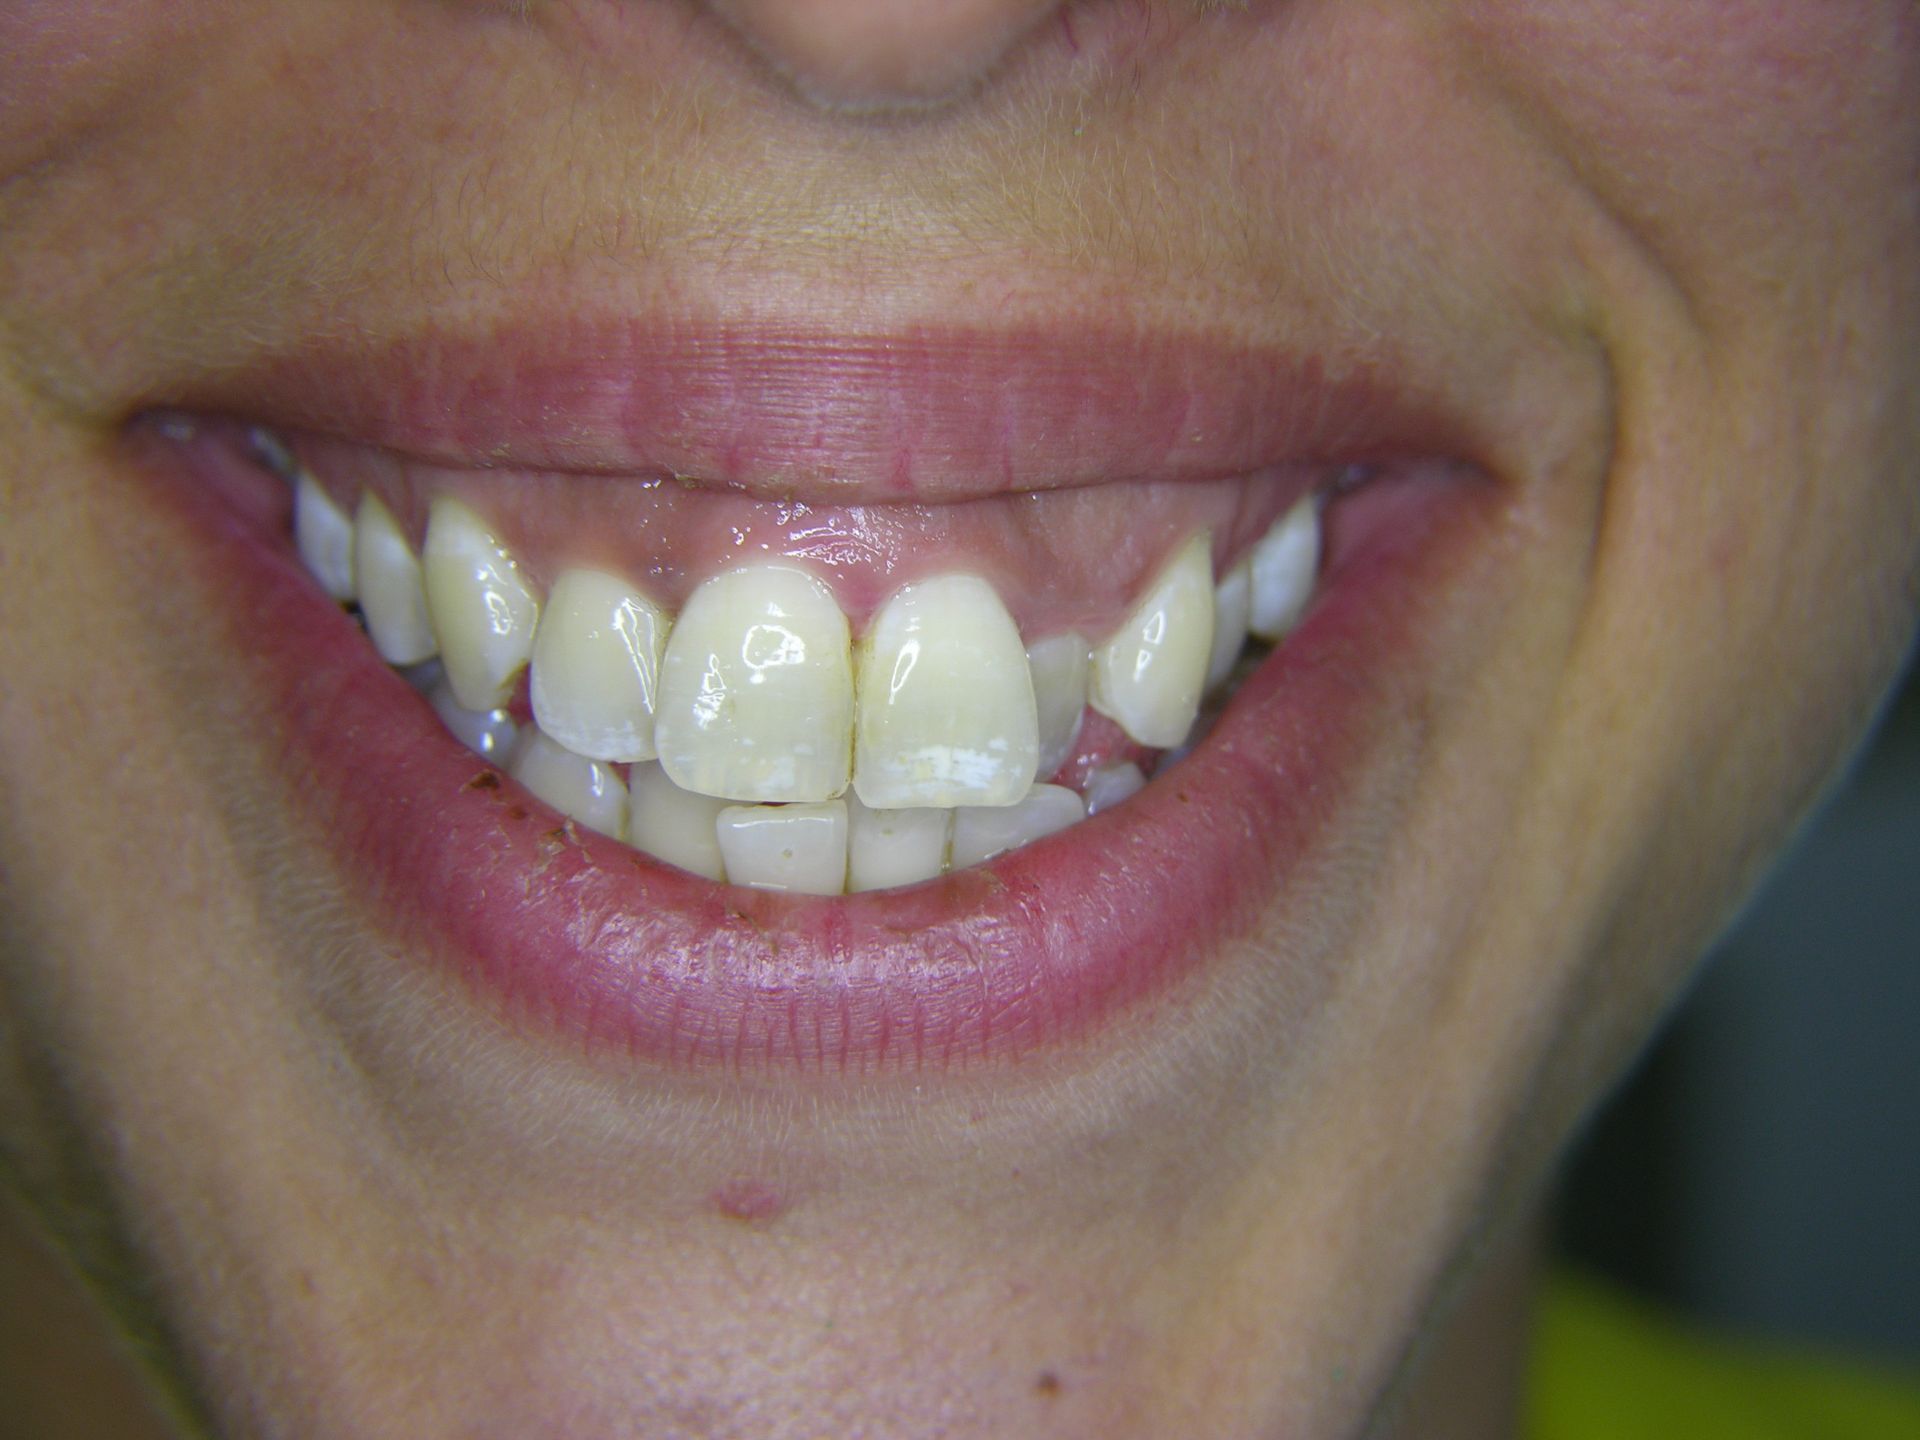

Beispiele von Versorgungen